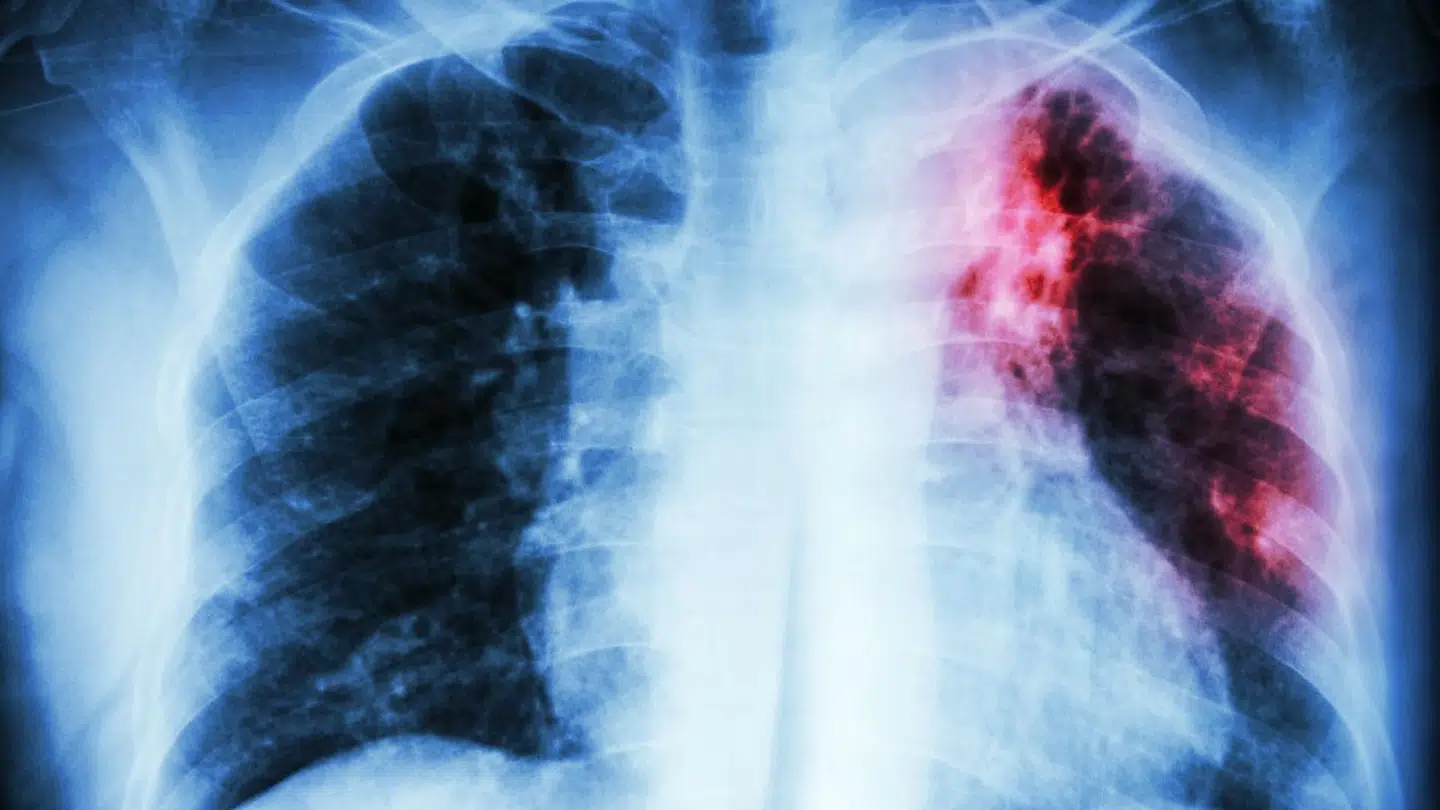

Statens Serum Institut melder om fire nye tilfælde af multi-resistent tuberkulose i Danmark alene i år. Det er, hvad vi normalt ser på to år, siger eksperterne.

De seneste mange år har der årligt været cirka to tilfælde af den frygtede lungesygdom herhjemme. Nu bemærker eksperterne fra Statens Serum Institut imidlertid, at der i løbet af årets fem første måneder allerede har været fire tilfælde.

Udviklingen bekymrer forskerne. Det er nemlig ikke bare en alvorlig sygdom, som er dyr og besværlig at behandle. Sygdommen er også forbundet med mange komplikationer og bivirkninger for den enkelte patient.

Sygdommen multi-resistent tuberkulose er en af de største trusler på verdensplan. I Danmark bliver langt de fleste helbredt, men i resten af verden kan man kun helbrede omkring halvdelen af de cirka 500.000 multi-resistente patienter.

Der går cirka halvandet år fra en person får stillet diagnosen, til patienten er rask, og hver behandling koster cirka en million kroner.